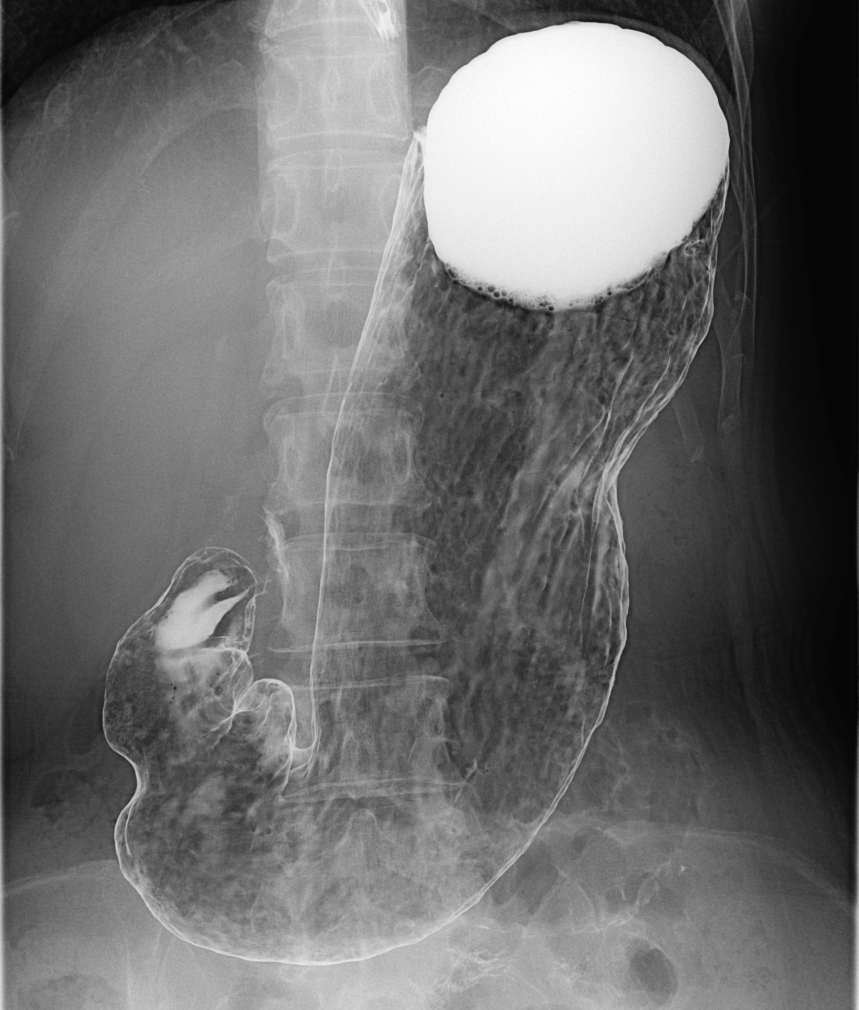

X線透視

当院ではFUJI製とCanon製のX線透視装置を導入しています

透視装置はX線を断続的に照射しながら画像にすることで、消化管の動きや造影剤の流れ、カテーテルの位置などをその場で確認することができます。

主な検査や治療の内容として、胃透視(胃がん健診)、透析患者さんへのシャントPTA(経皮的血管形成術)、カテーテルやチューブの挿入・確認、ERCP(内視鏡的逆行性胆道膵管造影)等の内視鏡を併用した治療などを行っています